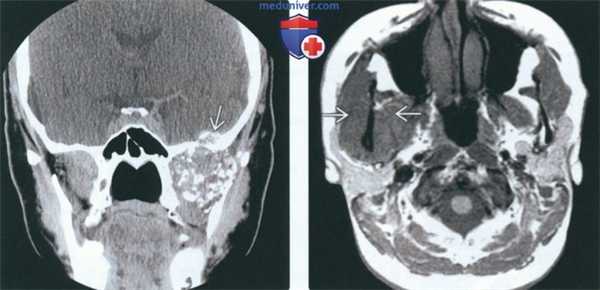

(Слева) МРТ Т1ВИ FS с КУ, аксиальная проекция. Лейомиосаркома жевательного пространства высокой степени злокачественности. Опухоль неоднородно накапливает контраст и прорастает в нижнюю челюсть. Только по данным лучевой диагностики дифференцировать различные типы сарком невозможно, за исключением случаев обнаружения матрикса остео- или хондросаркомы.

(Справа) МРТ Т1ВИ FS с КУ, коронарная проекция, тот же пациент. Новообразование, накапливающее контраст, распространяется в полость черепа через овальное отверстие. Отсюда опухоль может прорастать в пещеристый синус.

(Слева) На аксиальной МРТ (Т1 ВИ C+) в жевательном пространстве визуализируется лейомиосаркома высокой степени злокачественности, неравномерно накапливающая контраст и поражающая нижнюю челюсть. Большинство типов сарком жевательного пространства сложно дифференцировать в отсутствие костного или хондроидного матрикса.

(Справа) На корональной МРТ (Т1 ВИ С+ FS) у этого же пациента визуализируется контрастирующаяся опухоль с интракраниальным распространением через овальное отверстие а и поражением кавернозного синуса.